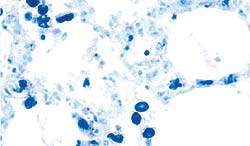

Technique "d'hybridation in situ" - Poumon.

Présence de génome de PCV2 dans le cytoplasme de macrophages alvéolaires et interstitiels. |